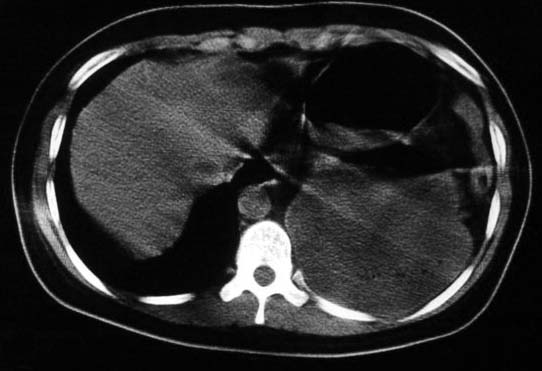

标题: CT5517:女性、24岁,反复胸痛、气促不能平卧半月。 [打印本页]

标题: CT5517:女性、24岁,反复胸痛、气促不能平卧半月。

左侧气液腔与胃腔影相连,考虑膈疝。钡餐检查有助于诊断。

我看这是膈疝,在纵隔窗第六\\七幅图像上可见胃粘膜影,再者可见两个腔影,这在液气胸是不会有的.

支持膈疝,纵隔窗内可见消化道的内容物。

左侧气液腔与胃腔影相连,考虑膈疝。口服urografin检查有助于诊断。